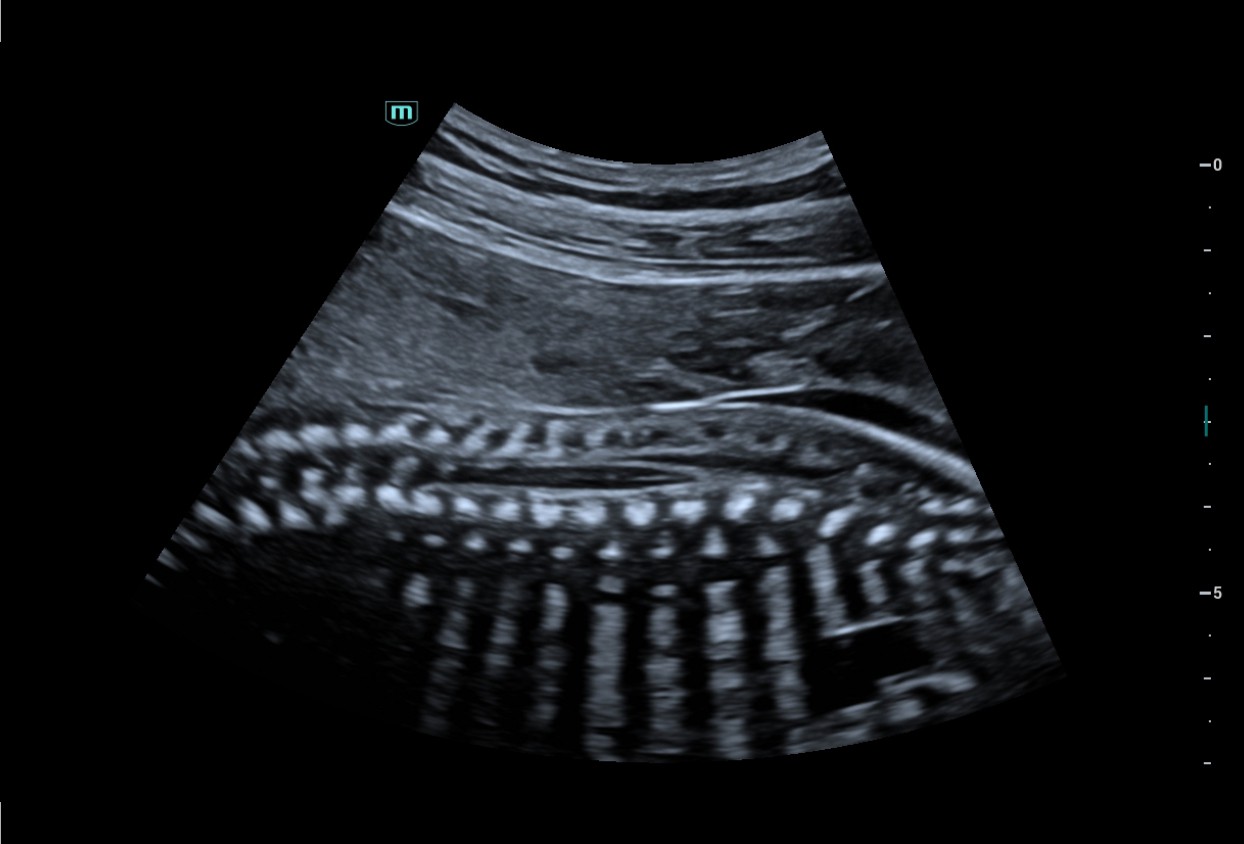

The Consona features new and concrete solutions, that efficiently help you to carry out smooth diagnoses for extensive type of patients. You will find highly powerful tools available on this series to keep you stay ahead in Obstetrics and Gynecology diagnosis.

Image Gallery